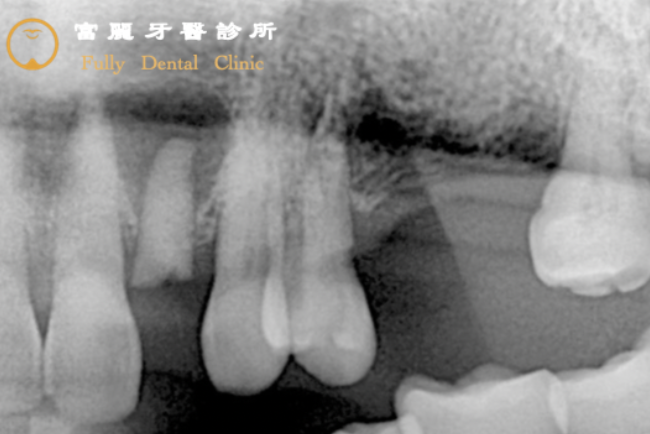

Before

原本套上牙套的牙根因為長時間沉重的咬力而整個劈開,加上對咬合功能十分重要的大臼齒缺失,造成患者的咀嚼能力大大降低,因此決定以植牙來恢復!